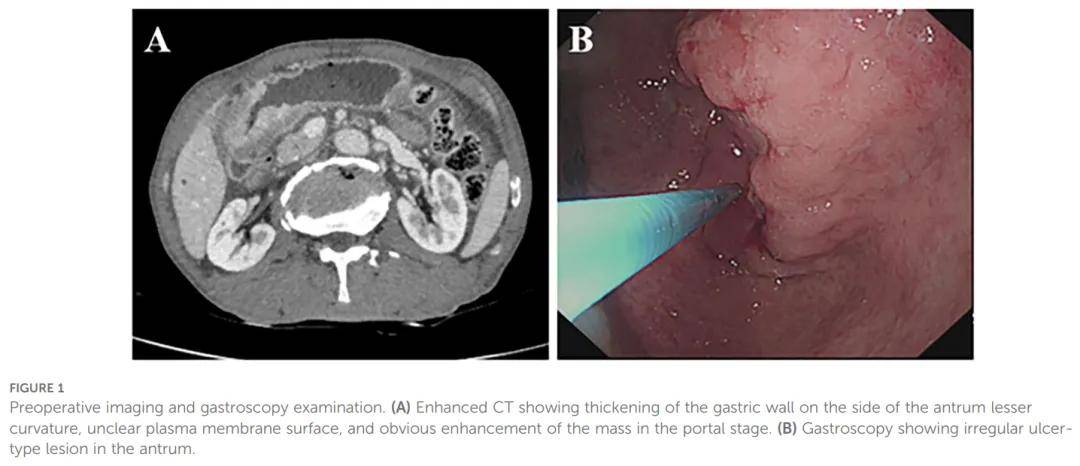

患者男,70 岁,因轻度上腹痛就诊于兰州大学第二医院,症状最早于入院前两个月出现。CT影像显示胃窦部胃壁增厚,伴明显强化(图1A)。胃镜检查发现胃窦部不规则溃疡性病变,边界不清,表面伴出血(图1B)。活检证实为鳞状细胞癌,血清肿瘤标志物(CEA、CA199、CA125、CA724、AFP)均在正常范围内。患者随后接受腹腔镜远端胃切除术联合淋巴结清扫术。术中见胃窦小弯侧一 7 cm大小肿瘤,穿透浆膜层并与横结肠系膜粘连。

▲图1 影像术前影像和胃镜检查结果